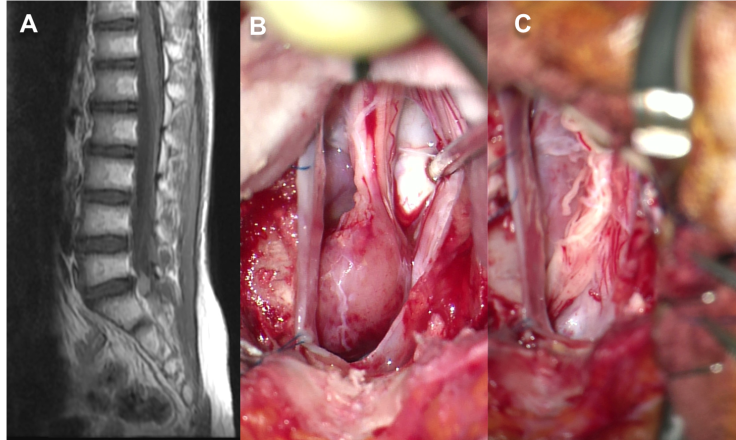

le schwannome

il est rare chez l’enfant, survenant alors souvent dans le cadre de la NF2, dont il peut être le premier signe.

il provoque des douleurs intenses, souvent nocturnes « au chant du coq ».

le traitement est chirurgical dans les lésions symptomatiques ou qui progressent.